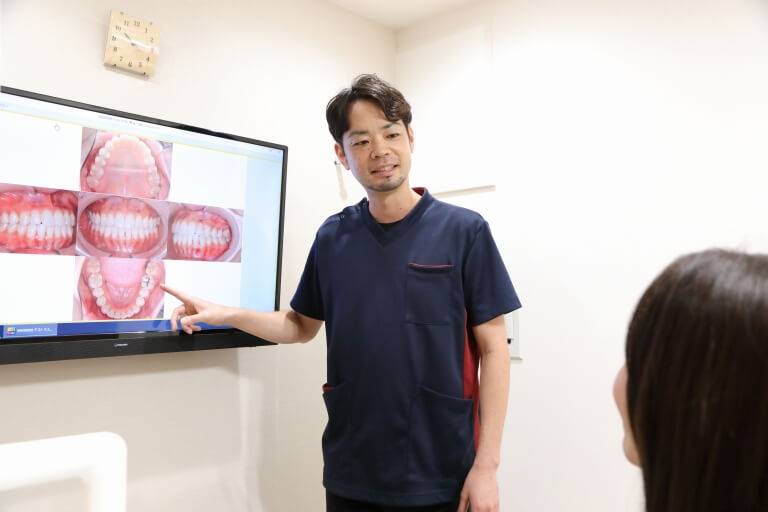

口腔内の写真撮影

患者さんがご自身のお口の状態を分かりやすく確認していただくために、お口の中の写真を撮影いたします。治療の進行具合の確認にも利用できます。

6お口全体の治療計画の説明

歯周病のコントロールを行いながら、検査結果を元に、現在のお口の状態を詳しくご説明させて頂きます。

歯周病のコントロールを行いながら、検査結果を元に、現在のお口の状態を詳しくご説明させて頂きます。

患者さんの考えや治療に対する思いをお聞かせ頂いた上で一緒に治療計画を考えていきます。今回問題が起こった原因を考え、将来再び悪くならないための治療を目指していければと思います。